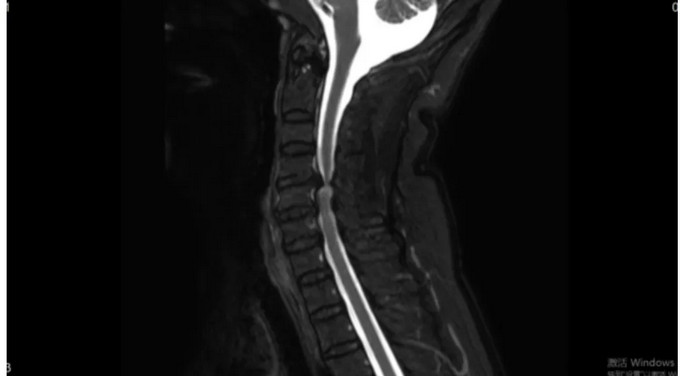

术后影像

颈椎CT矢状位

颈椎MRI矢状位 颈神经压迫程度明显减轻